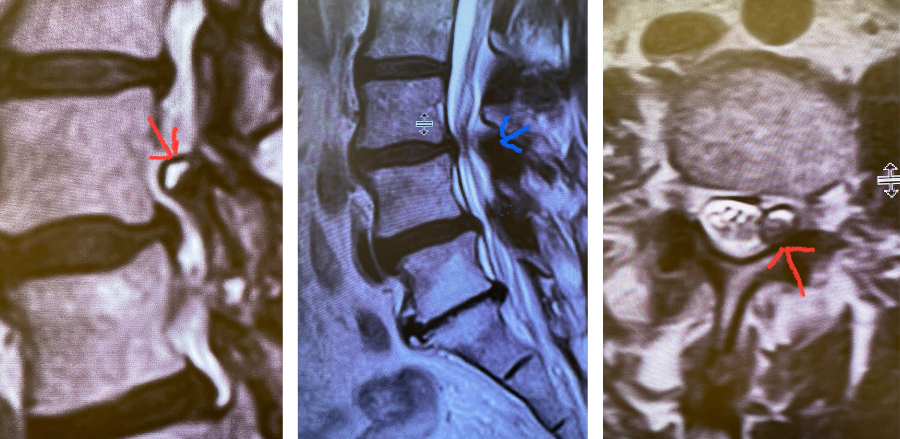

Fig 1: Sagittal and axial T2-weighted MRI images demonstrating a large superiority-oriented synovial cyst (red arrow) at L4-5. The cyst is below the exiting L4 nerve root and hence compresses the descending L5 root. Note the additional thickened ligamentum flavum and slight spondylolistheses at L3-4 and L4-5 (blue arrow).

The patient also had a slight spondylolisthesis at L3-4 and L4-5. The patient failed all means of conservative management including medications, physical therapy, and epidural injections. The patient elected to proceed with a decompressive laminectomy and in-situ fusion. During the procedure we encountered a thick-walled cyst that melded with the dura. We first found the descending left L4 nerve root and separated the cyst and proceeded to in essence bite away the cyst with an instrument. We decompressed the L4 nerve root as it entered its foramina by removing the majority of the cyst wall. There was thick gray gelatinous material within the cyst. Part of the cyst wall seemed to be continuous with the dura and left it alone as it caused no pressure on the root. After our decompression we decided to perform an in-situ fusion as we had relative preservation of the joint complexes. Post operatively, she had an uneventful course with significant relief of her leg pain.